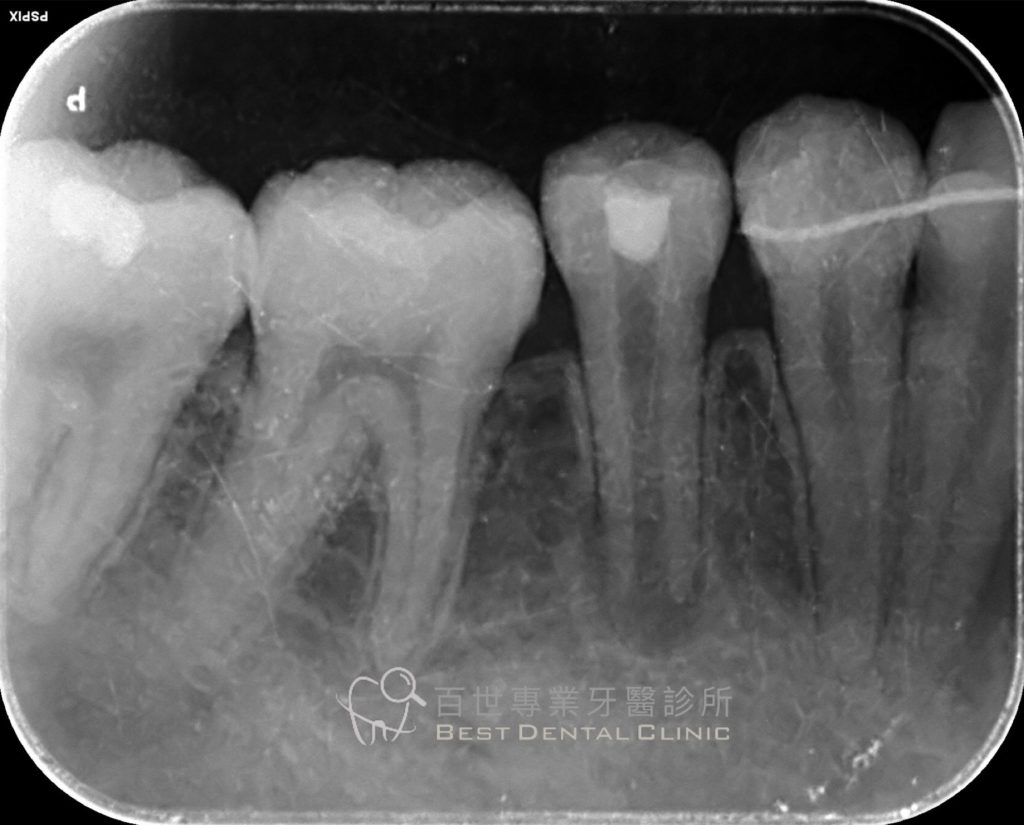

對容易斷裂的結節,可預先以樹脂材料加強保護。 - 根管治療與修復

若結節斷裂導致牙髓暴露,需進行根管治療,之後再以牙冠修復。